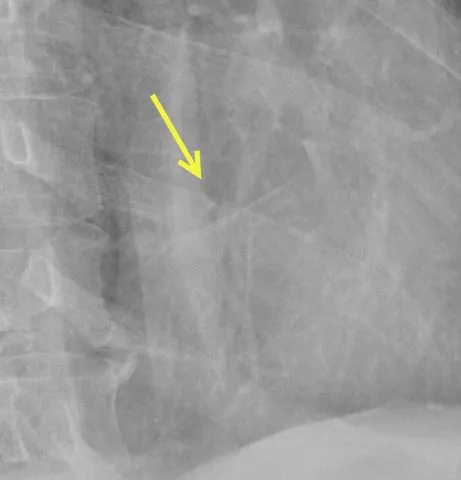

All I had was broken ribs on the left side. We were cleared to return to Tampa, left the ER at 10 PM, and caught an 11:07 PM flight.

When not out of alignment, rib fractures can be difficult to find, but this one seems rather obvious.